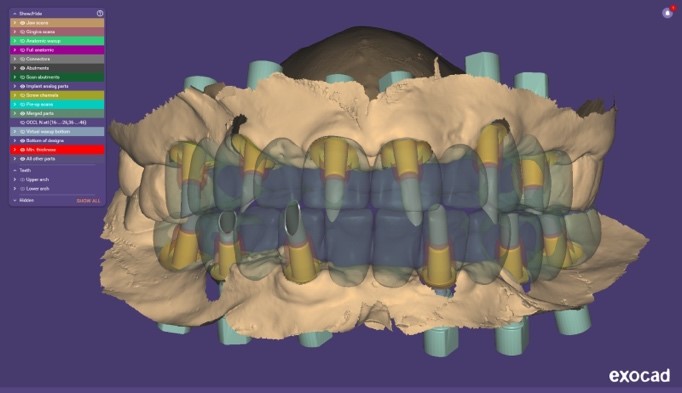

Si procedeva quindi alla scansione degli iPhysio® utilizzando uno scanner intraorale (IS 3600®, Dexis, Envista Holding Corporation, Brea, USA) (Fig. 4 a). Inviavamo i file STL al laboratorio odontotecnico per progettare e realizzare la protesi finale (Fig. 4 b,c,d,e,f).

Progetto CAD finale

Fig. 4(a)

Progetto CAD finale 2

Fig. 4(b)

Progetto CAD finale 3

Fig. 4(c)

Progetto CAD finale 4

Fig. 4(d)

Progetto CAD finale 5

Fig. 4(e)

Progetto CAD finale 6

Fig. 4(f) Progetto CAD finale della protesi.

Il laboratorio odontotecnico utilizzava le più recenti tecnologie CAD/CAM per produrre una protesi dentale personalizzata e di alta qualità che si adattasse perfettamente e garantisse funzionalità ed estetica ottimali. Il concetto iPhysio® facilita il recupero automatico del profilo di emergenza sottogengivale da parte dell'odontotecnico per la realizzazione di soluzioni personalizzate sia con la protesi cementata che con la protesi avvitata (Fig. 5 a,b,c). La paziente tornava per il posizionamento del restauro finale in zirconio avvitato (Fig. 6 a,b).